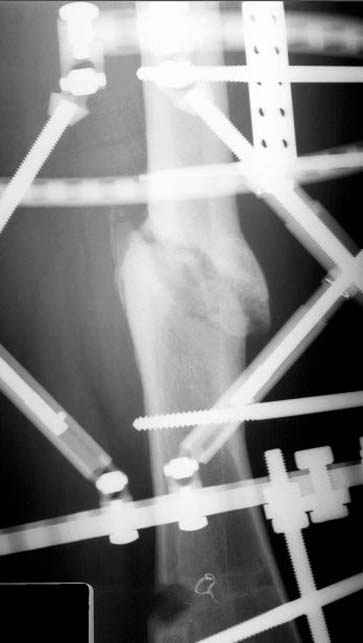

Отправитель: Djoldas Kuldjanov 23 Ноябрь 2004, 18:21

пластическая модель; и коррекция бедра аппаратом Илизарова.

Почему не замена гвоздя с рассверливанием, а аппарат?

Отправитель: Alexander Chelnokov 23 Ноябрь 2004, 21:29

Отправитель: Evgueny Tschekashkin 24 Ноябрь 2004, 21:09

хотя даже если бы и инфекция , то nail exchange с рассверливанием канала - вариант дебрайдмента) Я думаю, что последовательность развития событий:

Узкий к-м канал - тонкий гвоздь- усталостный перелом дистальных винтов - развитие нестабильности и как ее результат остеолиз вокруг гвоздя - деформация анатомической оси бедра. Похоже, что я понял почему аппарат, а не новый гвоздь:-)